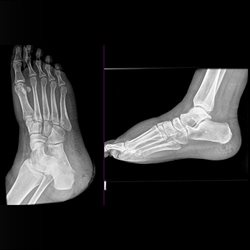

Various foot cases